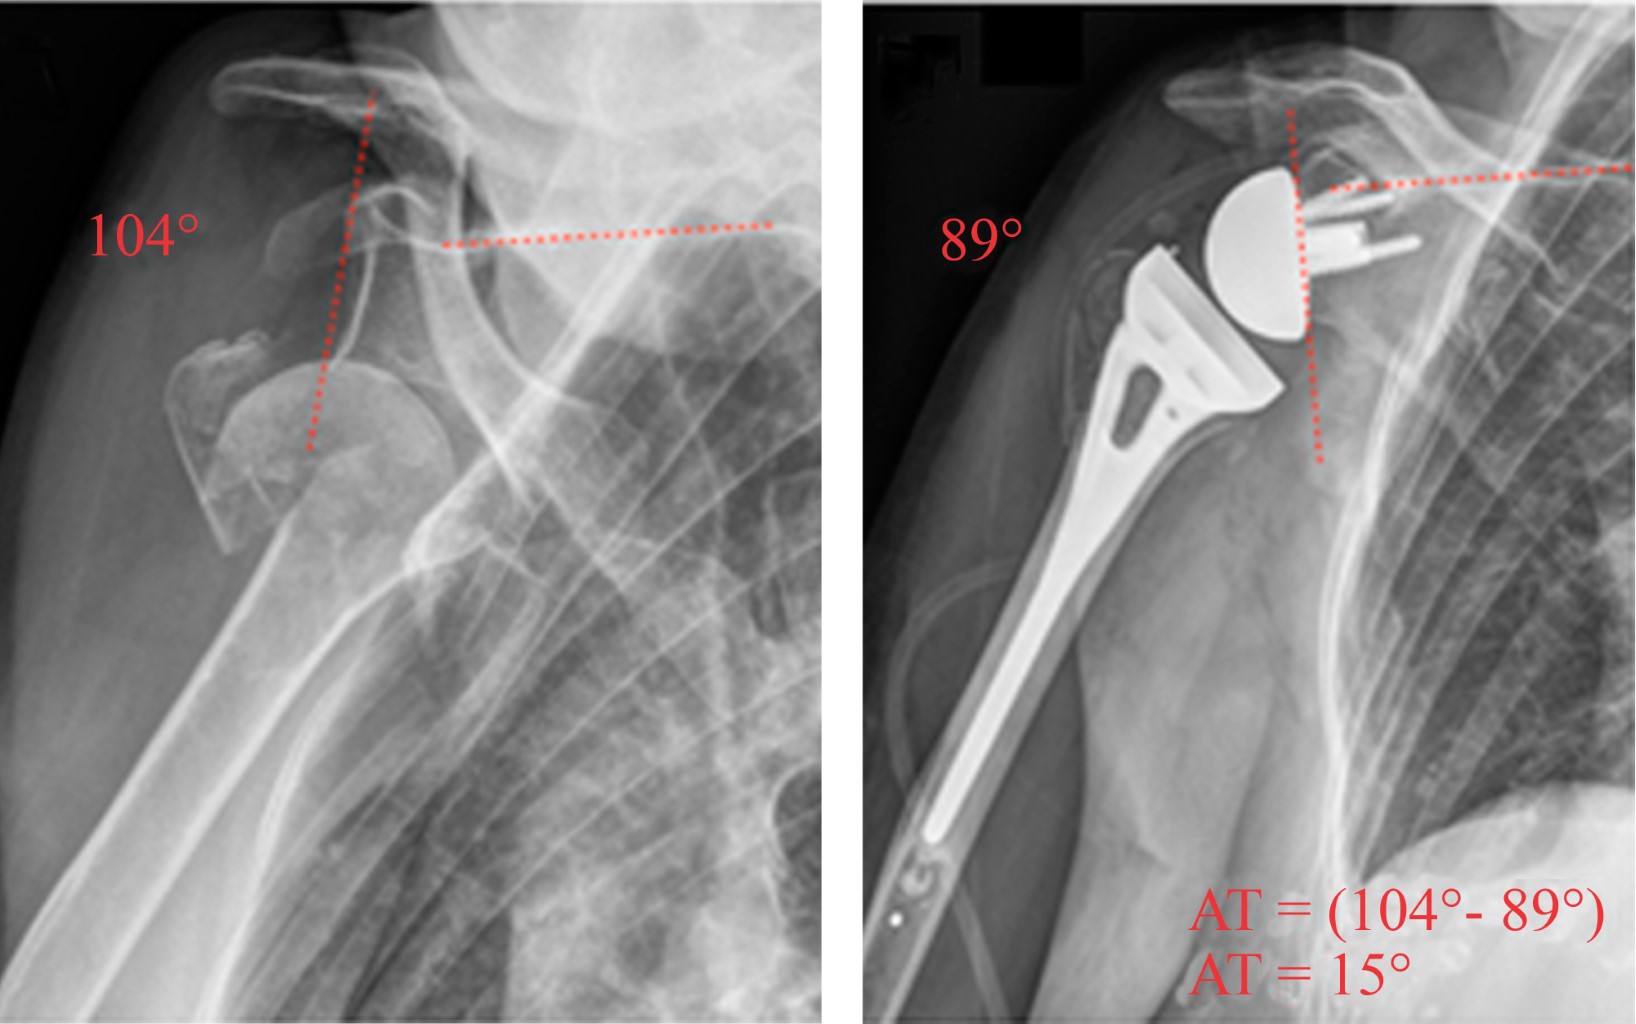

Purpose: Compare functional and radiological outcomes of three different designs of reverse shoulder arthroplasty according to distalization and lateralization shoulder angle, in heterogenic diagnostics (fracture, cuff arthropathy, fracture sequela and osteoarthritis). Material and methods: Prospective cohort of 33 patients of reverse shoulder arthroplasty (RSA) between December 2014 and July 2017 with a minimum one year of follow-up. We defined three groups, G: 10 patients with Grammont (155o, Medialized Glena), B: 9 patients with Bio-RSA (155º, lateralized bone glena) and A: 14 patients with Arrow (135o, lateralized metallic glena). We analyze demographic, clinical, functional and radiological outcomes (lateralization shoulder angle (LSA) and distalization shoulder angle (DSA)). For the statistical analysis, ANOVA, T-tests and linear regression tests were used, with a statistical significance of 5%. Results: The LSA was significantly higher in group A (98o A, 79o G, 80o B) (p < 0.05). In DSA, group B was significantly higher than A (52o B, 39o A) (p < 0.05) and not significant to G (48o G) (p = 0.06). There was no correlation of LSA and DSA with external rotation (p = 0.51) and active elevation (p = 0.41), respectively. There was no significant clinical (anterior elevation, external rotation, internal rotation) and functional outcomes (adjusted Constant score and subjective shoulder evaluation) differences between the different RSA models (p > 0.05). Conclusions: The LSA was higher in the Arrow and the DSA was higher in Bio-RSA. We did not find Clinical - Radiological correlation in this heterogeneous series of patients.

13. Ladermann A, Williams MD, Melis B, Hoffmeyer P, Walch G. Objective evaluation of lengthening in reverse shoulder arthroplasty. J Shoulder Elbow Surg. 2009; 18(4): 588-95. doi: 10.1016/j.jse.2009.03.012.

Figure 1